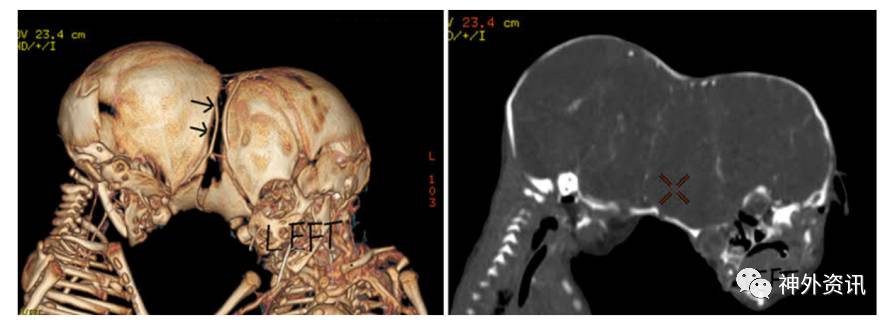

图3. 左图为CT成像的3D重建,见两颅骨间存有类似纤维连接(箭头);右图为CT增强片示两个婴儿的脑间有共同的静脉和动脉分支;提示左侧婴儿的大脑中动脉和右侧婴儿的大脑中动脉可能相吻合。